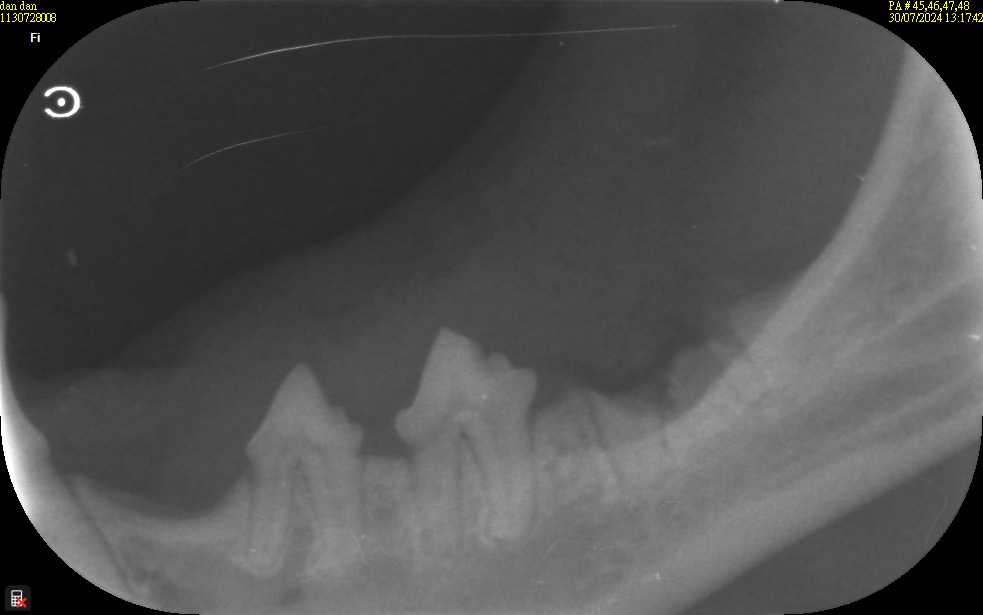

上個月才在他院摘的右眼,前天又突然發現下巴出血,醫生一看就sr 覺得案情可能不太單純,下巴這個洞又不像被咬傷的!! 摸摸嘴巴痛痛的,果然,打開口腔後發現左下顎前臼齒牙周出問題了!!

術前血液學評估有輕度的炎症相,所以手術中及術後都開立了抗生素及消炎止痛藥。另外,再針對左下顎進行局部麻醉,順利的幫小白的前臼齒移除,接著將牙周縫合後,再把下顎表皮破損處進行清創縫合。